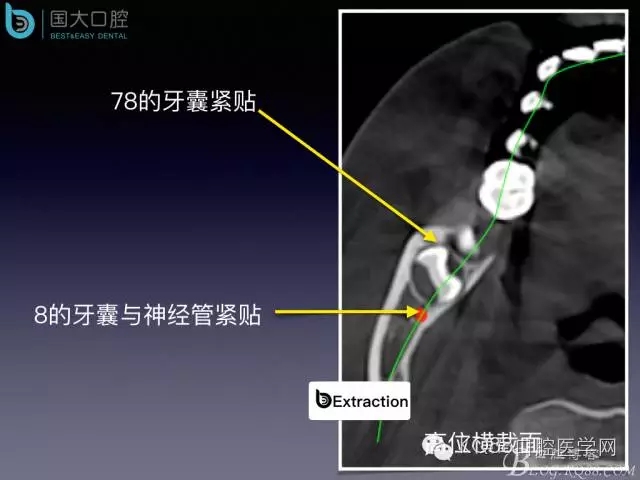

阻生牙的預(yù)防性拔除

- 牙齒拔除適應(yīng)證及第二磨牙遠中齲病